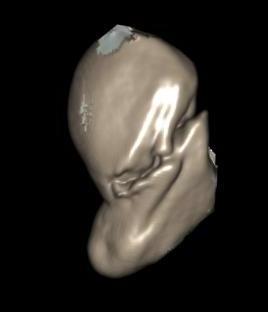

CT

Indication: any potential displacement

Position: patient prone with fully pronated hand over head

Instability

- displacement > 1mm on any film

- intra-scaphoid angle > 35o

- comminution

- proximal pole fractures

- perilunate trans-scaphoid dislocation

Scaphoid waist fracture 1 mm displaced

Scaphoid fracture with significant displacement

Scaphoid proximal pole fracture